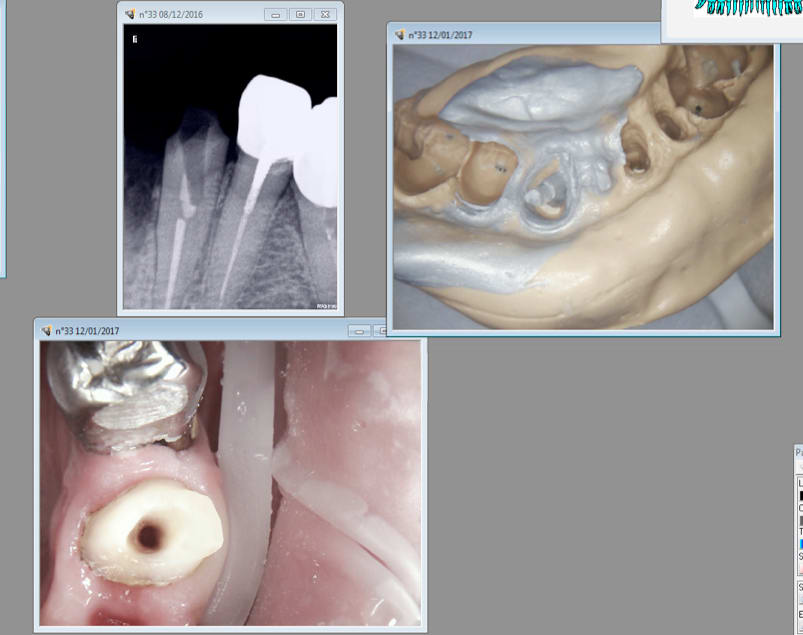

Viens de retourner voir image jointe.... le moignon est me semble-t-il félé, on voit une ligne sombre quart inferieur gauche de l'image qui semble démarrer à peripherie de la preparation et descendre jusque dans la lumière canalaire...

Après évidemment. Mais je ne suis pas joueur au point de continuer à essayer de virer le reste. .

C'est ca sauf que ca ne semble pas etre de travers. J'ai bien essayé de rectifier le tir mais quand ca veut pas ca veut pas. J'ai pas envie de foirer dans le sens vestibulo lingual en plus si ca n'est déjà fait. Il y a assez de dégâts comme ca. -)

Non.

Je voyais comme algi une solution de continuité entre racine et le coronaire, sans doute ta reconstitution pré endo, qui peut un peu te gener peut etre pour trouver ton bon axe.